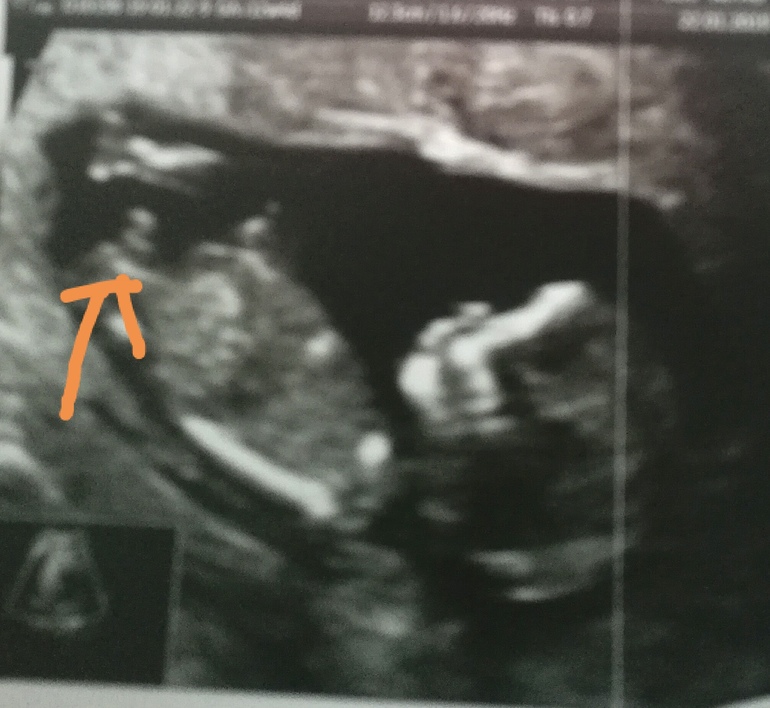

Вопросы про УЗИ, обследования и анализы: что, где, как, когда?Девочки, кто разбирается, скажите кто?)) видно что - то! На узи предположили мальчика!

Мне кажется, что как у девочки торчит, у мальчика вверх сильнее. Но не очень пока понятно. У нас сразу было ясно

На первом скрининге половой бугорок торчит у всех. У меня у девочки торчал почти параллельно телу, у мальчика ровно вертикально. Тут я думаю скорее мальчик)